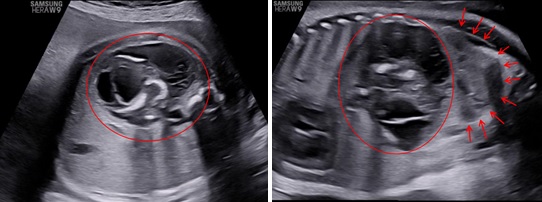

Siêu âm ngã bụng với máy HERA W9 (Samsung) ở các thời điểm 31 tuần 4 ngày, 34 tuần 3 ngày và 39 tuần. Ở hạ sườn trái và cực trên của thận trái có một khối không đồng nhất với kích thước tăng theo tuổi thai lần lượt là: 45x50x42mm, 48x58x50mm và 80x74x66mm. Bên trong khối này thấy hình ảnh vôi hoá có dạng của xương vòm sọ, xương đùi, xương sống và hình ảnh các cấu trúc này rõ khi tuổi thai lớn hơn. Trên Doppler màu, có một mạch máu nuôi khối này xuất phát từ động mạch chủ bụng của thai vật chủ với dạng sóng của động mạch rốn.

Hình 1: Thai 31 tuần 4 ngày, mặt cắt ngang và dọc bụng thai cho thấy một khối không đồng nhất nằm ở vùng hạ sườn trái dưới cơ hoành (hình tròn), đẩy thận trái xuống dưới (hình mũi tên).

Hình 2: Thai 34 tuần 2 ngày, mặt cắt ngang và dọc bụng cho thấy trong khối này có các cấu trúc giống vòm sọ (dấu sao) và cột sống và xương đùi (mũi tên)